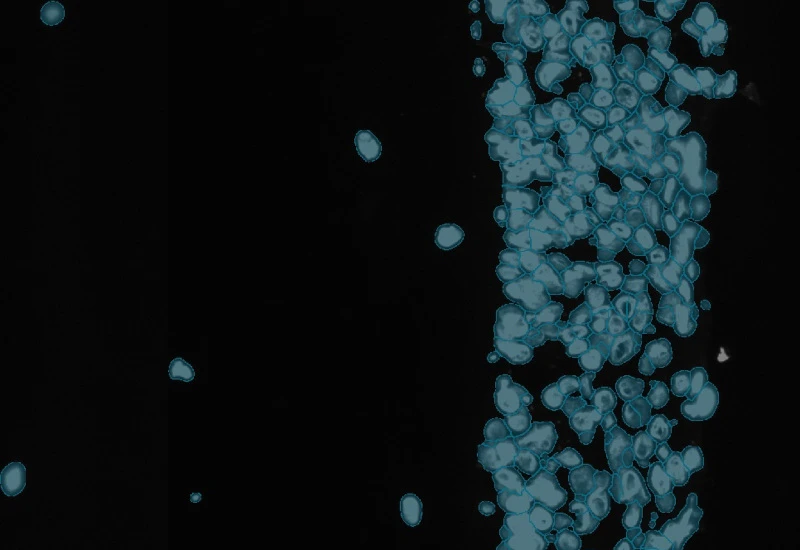

The IF Artificial Skin App stratifies skin equivalents into differnet layers including dermis and epidermis and identifies nuclei based on appropriate staining. Further is subclassifies epidermis into stratum corneum, high suprabasal, low suprabasal, basal. The App outputs, area (µm2) of epidemis and dermis, area and mean staining intensity for each sublayer of the epidermis, total number of nuclei for each layer/sublayer and number/% of marker positive cells for each layser and sublayer.

Image courtesy of Prof. Florian Gruber

Detection of dermis and epidermis

Detection of epidermis sublayers